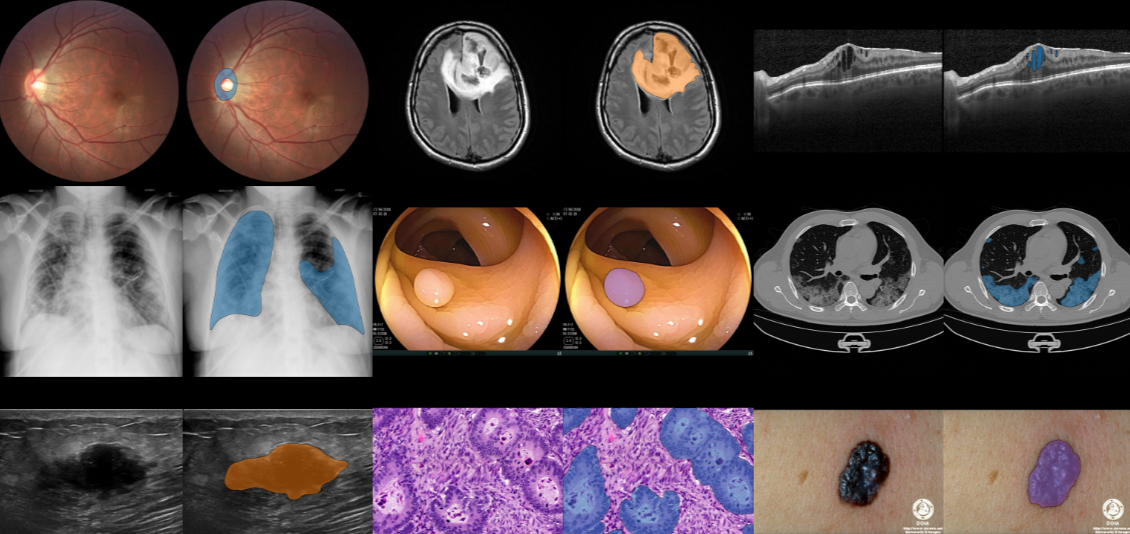

Study: A foundation model for joint segmentation, detection and recognition of biomedical objects across nine modalities. Image Credit: Microsoft Research

In a recent study published in the journal Nature Methods, researchers at Microsoft Research, Providence Genomics, Earle A. Chiles Research Institute, Providence Cancer Institute, and the Paul G. Allen School of Computer Science and Engineering, University of Washington developed "BiomedParse," a groundbreaking biomedical foundation model for image analysis that can jointly perform image segmentation, object detection, and object recognition across nine major imaging modalities. They found that BiomedParse outperformed existing methods, particularly on irregularly shaped objects, and enabled new capabilities like segmenting and labeling all objects in an image using textual descriptions.

BiomedParse uses a modular design based on the SEEM (Segment Everything Everywhere All at Once) architecture. It includes an image encoder, a text encoder, a mask decoder, and a meta-object classifier for joint training with semantic information. The system operates without bounding boxes, contrasting with state-of-the-art methods like MedSAM. Instead, BiomedParse uses text prompts for segmentation and recognition, allowing broader scalability. Evaluation metrics included Dice scores for segmentation accuracy and silhouette scores for embedding quality. Tests were also used to measure BiomedParse’s ability to detect invalid text prompts using statistical methods, including the Kolmogorov–Smirnov test. The system’s performance was validated across nine imaging modalities, including pathology, computed tomography (CT), magnetic resonance imaging (MRI), ultrasound, X-ray, fluorescence microscopy, electron microscopy, phase-contrast microscopy, and brightfield microscopy. The results were compared to those of other segmentation models, such as the Segment Anything Model (SAM) and Medical SAM (MedSAM).